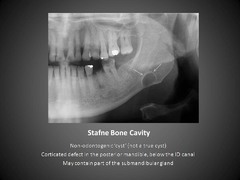

Depression on the mandible at the inferior alveolar canal- submandibular gland a)Ranula b)Pleomorphic adenoma c)epidemic parotitis (mumps) d)Stafne's bone cyst

Front

Stafne's bone cyst

Back